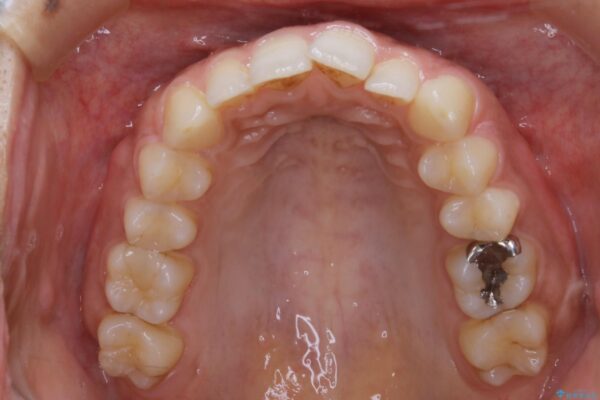

気になるガタツキと噛み合わせを改善したいとご来院されました。

下の歯列よりも上の歯列が前に出ている状態を治すため、マウスピース矯正に加え、患者様にゴムかけのご協力をいただきました。その結果、ガタつきが改善し、上下の噛み合わせが適切な位置で合うようになりました。